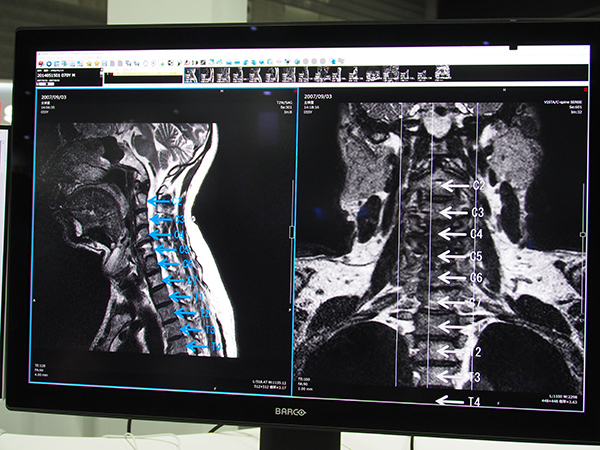

今回のバージョンアップでは,脊椎ラベリングをアノテーションとして保存できる機能が追加された。サジタル画像に対して脊椎にマニュアルでラベリングを行うと,脊椎番号がアノテーションとして保存され,アキシャルなど別の断面で表示したときにも,連動して脊椎番号が表示され読影をサポートする。ラベリング方法はユーザーごとに設定でき,ラベリングを開始する脊椎とラベリングの方向(C1から尾側へ,T12から頭側へなど)をプリセットしておくことで,脊椎を指定していくだけで自動的に番号が振られる。

「EV Insite R」に追加された脊椎ラベリングをアノテーションとして保存する機能

アノテーションは各断面に連動し,アキシャル表示では右上に脊椎番号が表示され読影を支援する

ラベリングの方法はユーザーごとにプリセットが可能